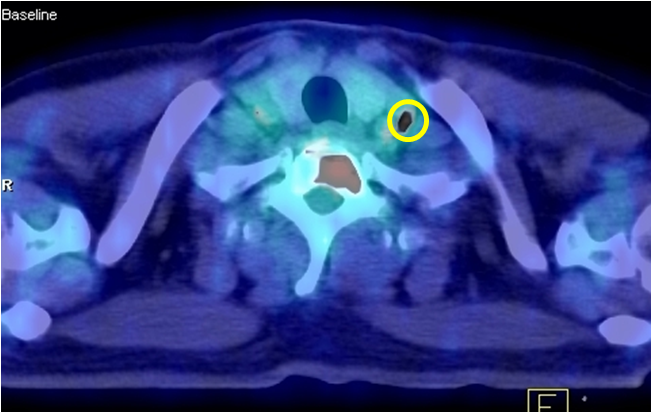

Hình 2: Hình ảnh chụp cắt lớp vi tính (CT) lồng ngực: có khối u phổi trái (trong vòng tròn màu vàng)

Kết quả giải phẫu bệnh: ung thư biểu mô tuyến.